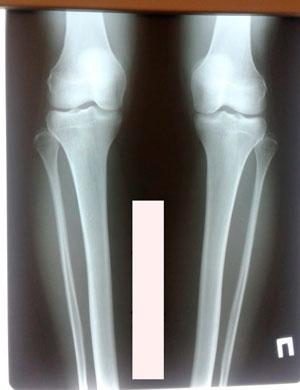

Исходник - 24 года.

Диагноз: варусная деформация голеней. Ротация с обеих сторон.

Дата операции - 16.10.2019г.